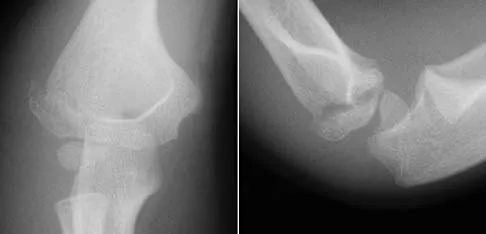

A 78-year-old woman falls onto her nondominant left elbow and sustains the injury shown in Figure 5. What treatment option allows her the shortest recovery time and highest likelihood of good function and range of motion?

Explanation

Total elbow arthroplasty has become the treatment of choice for complex, comminuted distal humeral fractures in patients older than age 70 years. It yields a faster recovery with more predictable functional outcomes, although limitations of lifting weight of more than 5 pounds must be followed to avoid loosening. Kamineni S, Morrey BF: Distal humeral fractures treated with noncustom total elbow replacement. J Bone Joint Surg Am 2004;86:940-947.